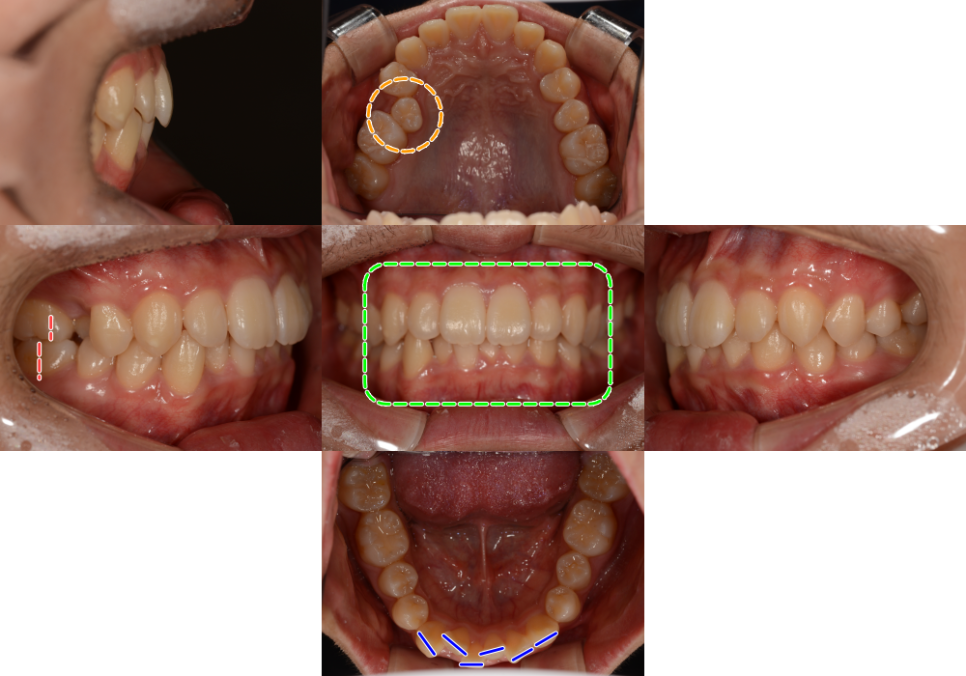

24.05.13

24.09.24

이후 어느 정도 당겨졌다면

브라켓을 부착해

세부 조정을 진행합니다.